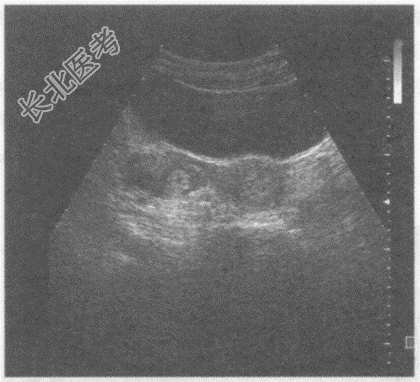

- 单项选择题临床资料:女性患者, 30岁,自诉停经40天, 腹痛伴阴道出血4天。检验:尿妊娠试验阳性。

超声综合描述: 子宫形态大小正常,宫腔内未见胎囊。右卵巢内见无回声, 周边呈环状中强回声,CDFI: 周边可见血流信号。见下图及彩图。

超声提示: A、右卵巢癌

B、右卵巢黄体囊肿

C、右卵巢异位妊娠

D、右卵巢卵泡

E、右卵巢黄素囊肿